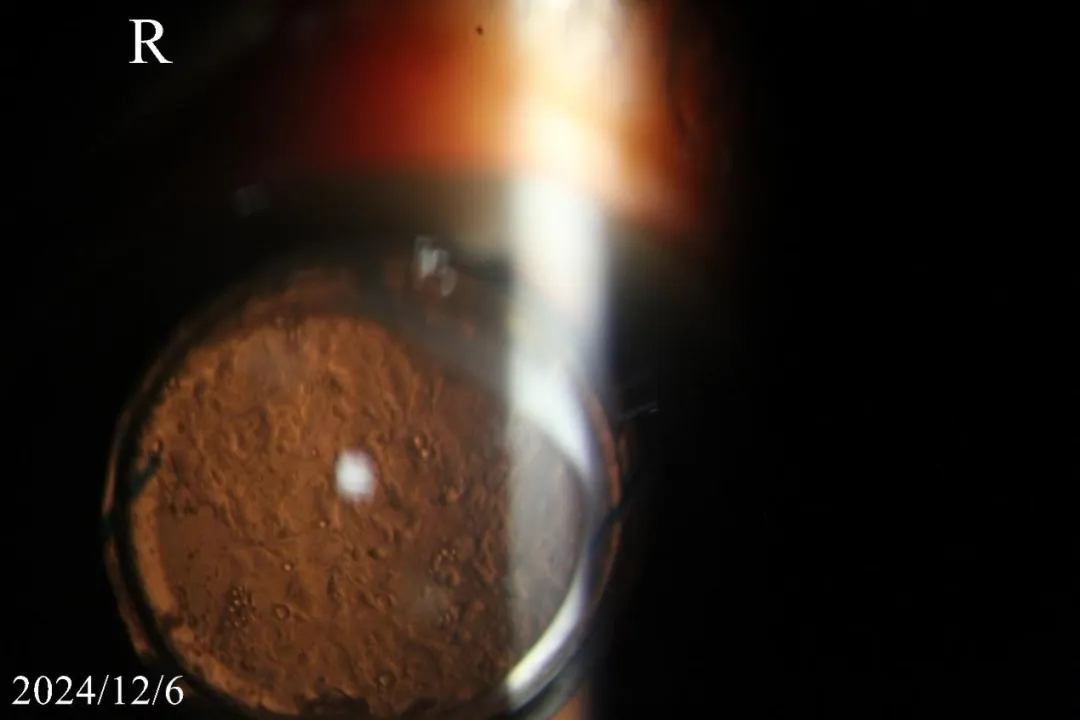

专科检查:右眼:裸眼视力0.05,矫正视力0.08,左眼:裸眼视力:0.4,矫正视力0.7-;眼压:右眼16.9mmHg,左眼19.1mmHg。裂隙灯检查:右眼人工晶状体(IOL)在位,IOL后表面与后囊膜之间存在间隙,后囊可见锅巴样混浊。

图2. 后囊可见锅巴样及空混浊泡。